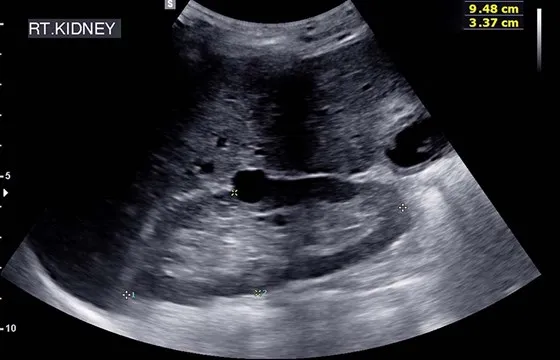

- USG układu moczowego: Badanie ultrasonograficzne pozwala ocenić nerki (ich wielkość, kształt, obecność kamieni, torbieli, guzów), pęcherz moczowy (pojemność, grubość ścian, obecność zalegającego moczu po mikcji) oraz moczowody. Jest to badanie nieinwazyjne i bezbolesne.